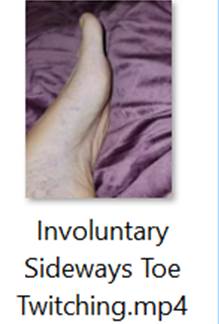

Patient is a 58 year old female physician with past medical history of high cholesterol, celiac disease and multiple food allergies who sustained an open crush fracture of the left big toe in June 2022 after a heavy double glass and metal shower door fell on her toe. She was seen in the ER and received wound care with tetanus booster and trephination of toenail. 2-3 days after injury intermittent twitching was noted in the small muscles surrounding the injured toe. One week after injury, twitching worsened around the medial left foot, progressed to the lateral toes of the left foot, then gradually progressed further up the left leg. Once twitching reached the gluteal muscles (ascending spread), it spread to the all extremities and back. There were several strong tonic contractions of gluteal muscles which lifted the patient off of the couch involuntarily. At this time patient had concern for tetanus and sought initial ID consult. Labs done included Creatinine Kinase which was 602 with normal CBC, CMP and negative blood cultures.

Patient was hospitalized in August 2022 for IV (Intravenous) metronidazole which helped reduce (but not eliminate) symptoms for about one month. MRI of the left toe showed still healing fracture and ortho consult did not recommend surgical intervention at that time. Multiple neurology consults were obtained to rule out neurological cause of symptoms given the unusual presentation and all neurology consults felt this was not primarily a neurological issue and she was referred back to Infectious Disease for management. EMG & MRI of the brain were done and were both normal. (Patient was advised to continue benzodiazepine during initial EMG so any possible exaggerated F-response and spasms were suppressed by benzodiazepines during the EMG). During all physical exams involuntary muscle spasms/ twitching of the left foot/toes were noted involving both agonist and antagonist muscles.

1) Videos of Left Toe & Foot Spasms/Twitching: